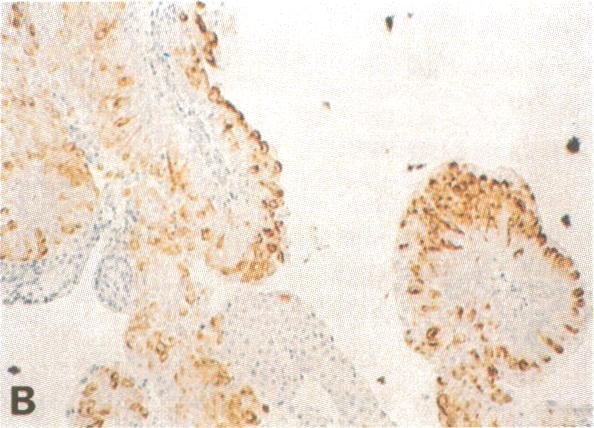

Three mouse monoclonal antibodies (mAbs), which define a highly restricted antigen, were obtained by simultaneous immunizations with superficial papillary bladder tumor cells and mouse polyclonal serum against normal urothelium. The antigen was detected by the avidin/biotin/peroxidase method in 30/44 superficial bladder tumors (68%) but in only 4/27 infiltrating urothelial cancers (with much less intensity). No normal adult or fetal tissues tested expressed the antigen, including normal urothelium from 40 individuals, 13 of whom had a bladder tumor positive for the antigen. Only 1 of 45 nonbladder tumors showed some reactivity with one of the three mAbs. Serological tests on a large panel of human cancer cell lines and normal cultured cells were negative. The antigen is highly stable and well preserved on paraffin-embedded tissues. Electrophoretic transfer blot experiments with fresh tumor extracts showed that all three mAbs react with a determinant on a component of 300,000 Mr (pI 9.5) and 62,000 Mr (pI 6.5). The antigen shows polymorphic expression at the cellular level on tissue sections and also at a molecular level on immunoblots where the two bands are differentially detected on extracts of a series of tumors but are not visualized on normal urothelium extracts. The characteristics of this antigenic system suggest that it may provide some insights about the biology of bladder cancer. Specific detection of the antigen on 70% of superficial bladder tumors with normal cytology may be useful for their diagnosis and follow-up.

通过用浅表乳头状膀胱肿瘤细胞和抗正常尿路上皮的小鼠多克隆血清同时免疫,获得了三种定义高度受限抗原的小鼠单克隆抗体(mAb)。采用抗生物素蛋白/生物素/过氧化物酶法在30/44例浅表膀胱肿瘤(68%)中检测到该抗原,但仅在4/27例浸润性尿路上皮癌中检测到(强度低得多)。所检测的正常成人或胎儿组织均未表达该抗原,包括40例个体的正常尿路上皮,其中13例膀胱肿瘤抗原呈阳性。45例非膀胱肿瘤中只有1例与三种mAb之一有一定反应性。对大量人类癌细胞系和正常培养细胞进行的血清学检测均为阴性。该抗原在石蜡包埋组织上高度稳定且保存良好。用新鲜肿瘤提取物进行的电泳转移印迹实验表明,所有三种mAb均与分子量为300,000(pI 9.5)和62,000(pI 6.5)的一种成分上的决定簇发生反应。该抗原在组织切片的细胞水平以及免疫印迹的分子水平上均显示多态性表达,在一系列肿瘤提取物中可分别检测到两条带,但在正常尿路上皮提取物中未显现。该抗原系统的特征表明,它可能为膀胱癌的生物学特性提供一些见解。在70%细胞学正常的浅表膀胱肿瘤中特异性检测该抗原可能对其诊断和随访有用。